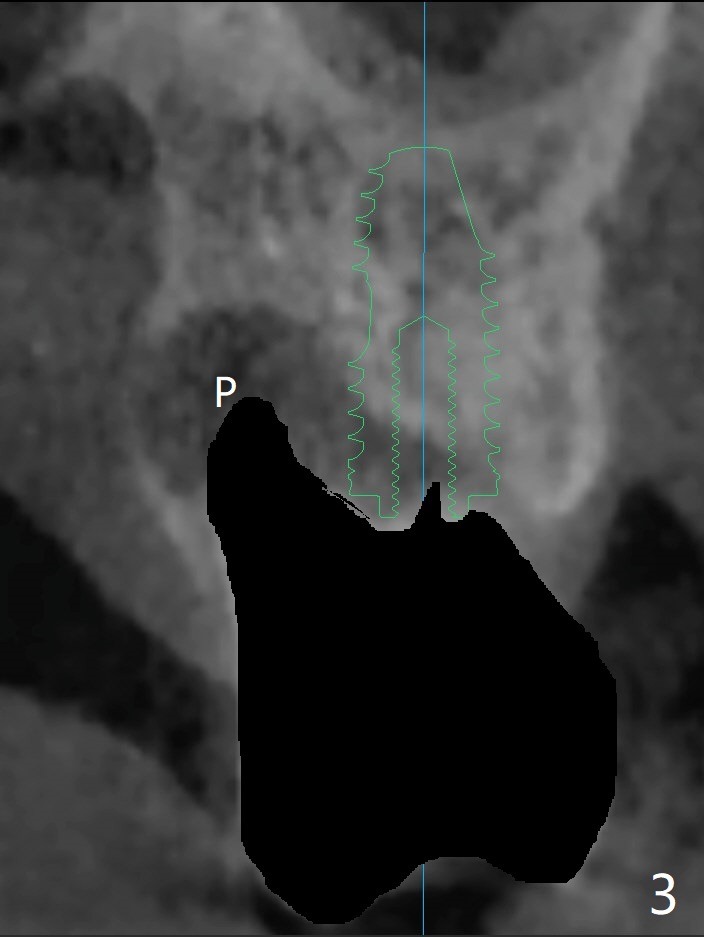

尽管腭侧(P)根周围骨质吸收严重(图三(术前设计)),15号牙拔除还挺困难,因为两个颊侧根骨质吸收不明显,而腭侧根表面许多结石(说明牙周病变)。导板使用中,金属圈脱落,插回后还能用(图一(术后拍摄)),完成种植(图二)。金属圈脱落可能是因为近中塑料太少了(图一,二:箭头)。植体(图四:绿色)和基台(粉红色)放置后,粘性骨粉植骨(红圆圈)前,在腭侧缺失处塞入一块胶原塞(浅蓝色),最后缺损充填完善(图二,五比较(*))。